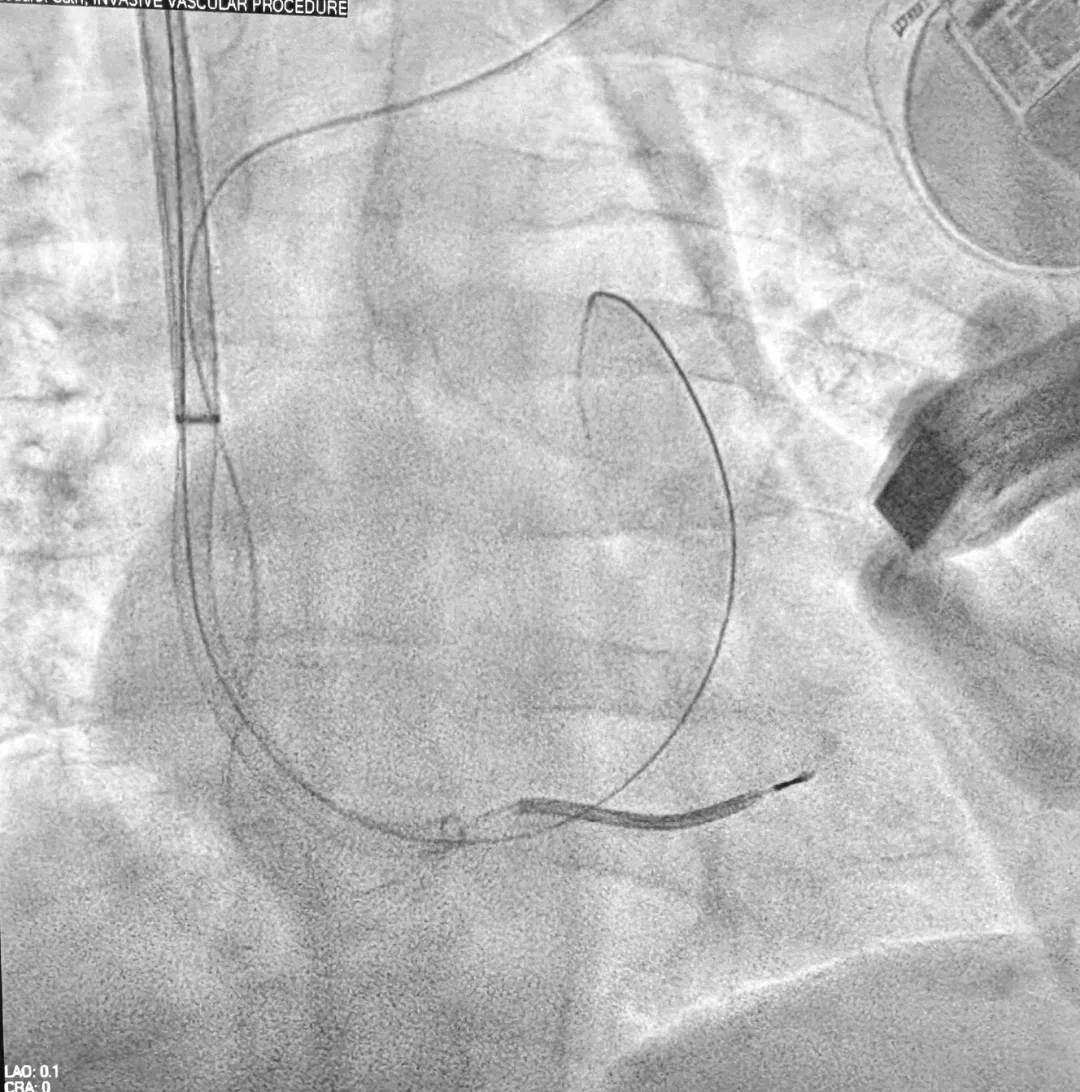

图2

24F导管引导20F导管进入右心室心尖部(使用Inari FlowTriever系统)